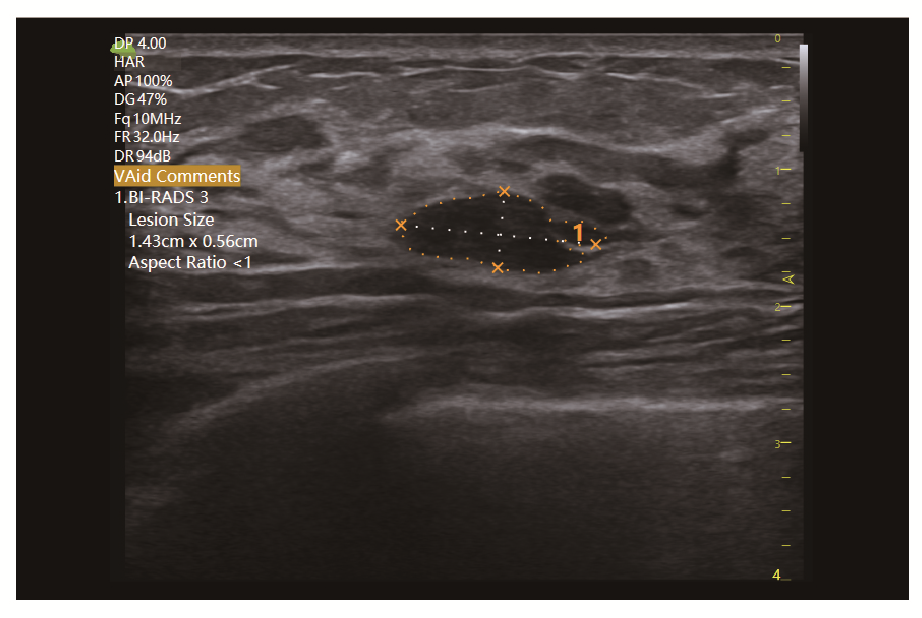

Клінічні зображення, що демонструють якість діагностики та можливості обладнання

Клінічне зображення 2